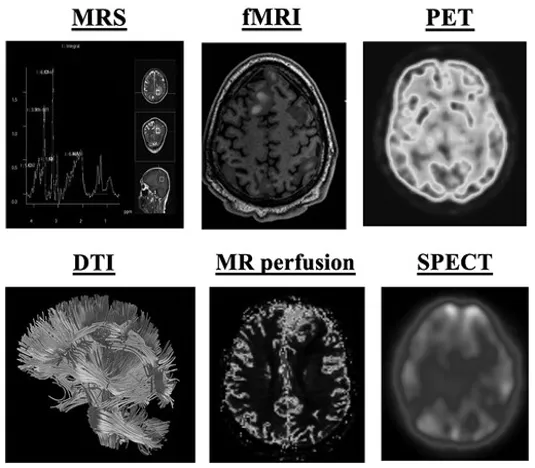

除常见CT与MRI外,哪些先进及新兴技术有助于更深入了解胶质瘤?主要包括磁共振波谱成像(MRS)、灌注加权成像(灌注MRI)、弥散张量成像(DTI)、功能磁共振成像(fMRI)、正电子发射断层扫描(PET)、单光子发射计算机断层扫描(SPECT)及其他新兴成像技术等。